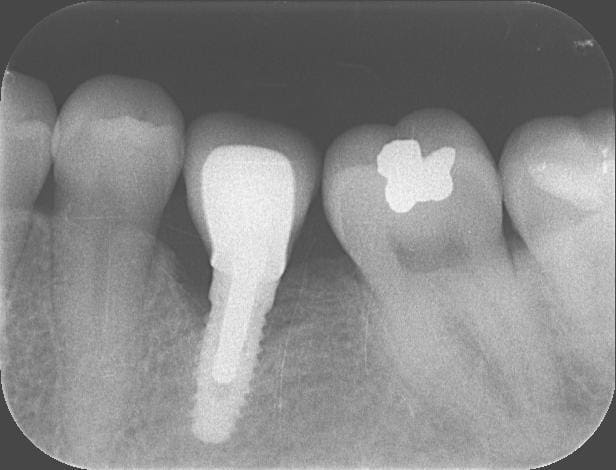

On parle depuis le début de 'cratérisation' pas de perte osseuse marginale, ou de remaniements post-chir etc ..

Quand j'ai vu les Rx présenté ici, j'ai eu la même réaction que mac, j'y ai plus vu des remaniements osseux physiologiques que pathologiques, et ces pertes osseuses ne me semblaient pas toutes mériter le terme de craterisation.

Voici trois Rx : cratère ou pas ? quel taux d'échec à 5 ans (tout les implants), ce sont les mêmes : 3I plateforme plate, deux temps chir, pas de plateform switching, pilier vissé prothèse scellée, 3 mois d'OI.